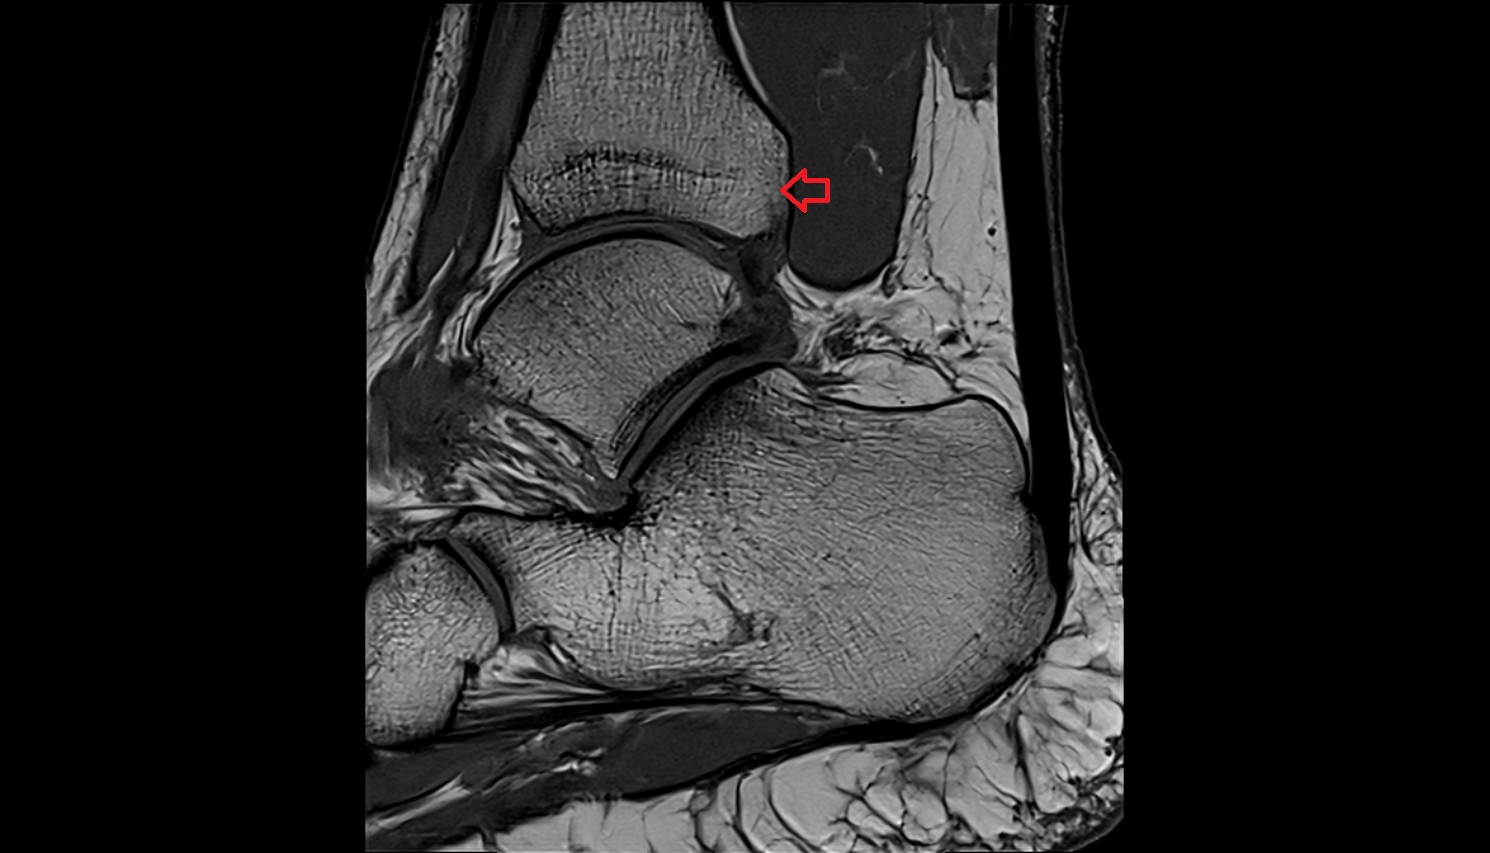

- Talus

- Body of talus

- Medial malleolus

- Lateral malleolus

- Ankle joint

- Achilles tendon